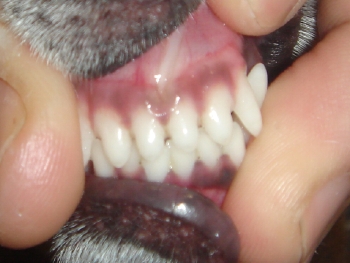

同犬種における正常な歯肉ライン。